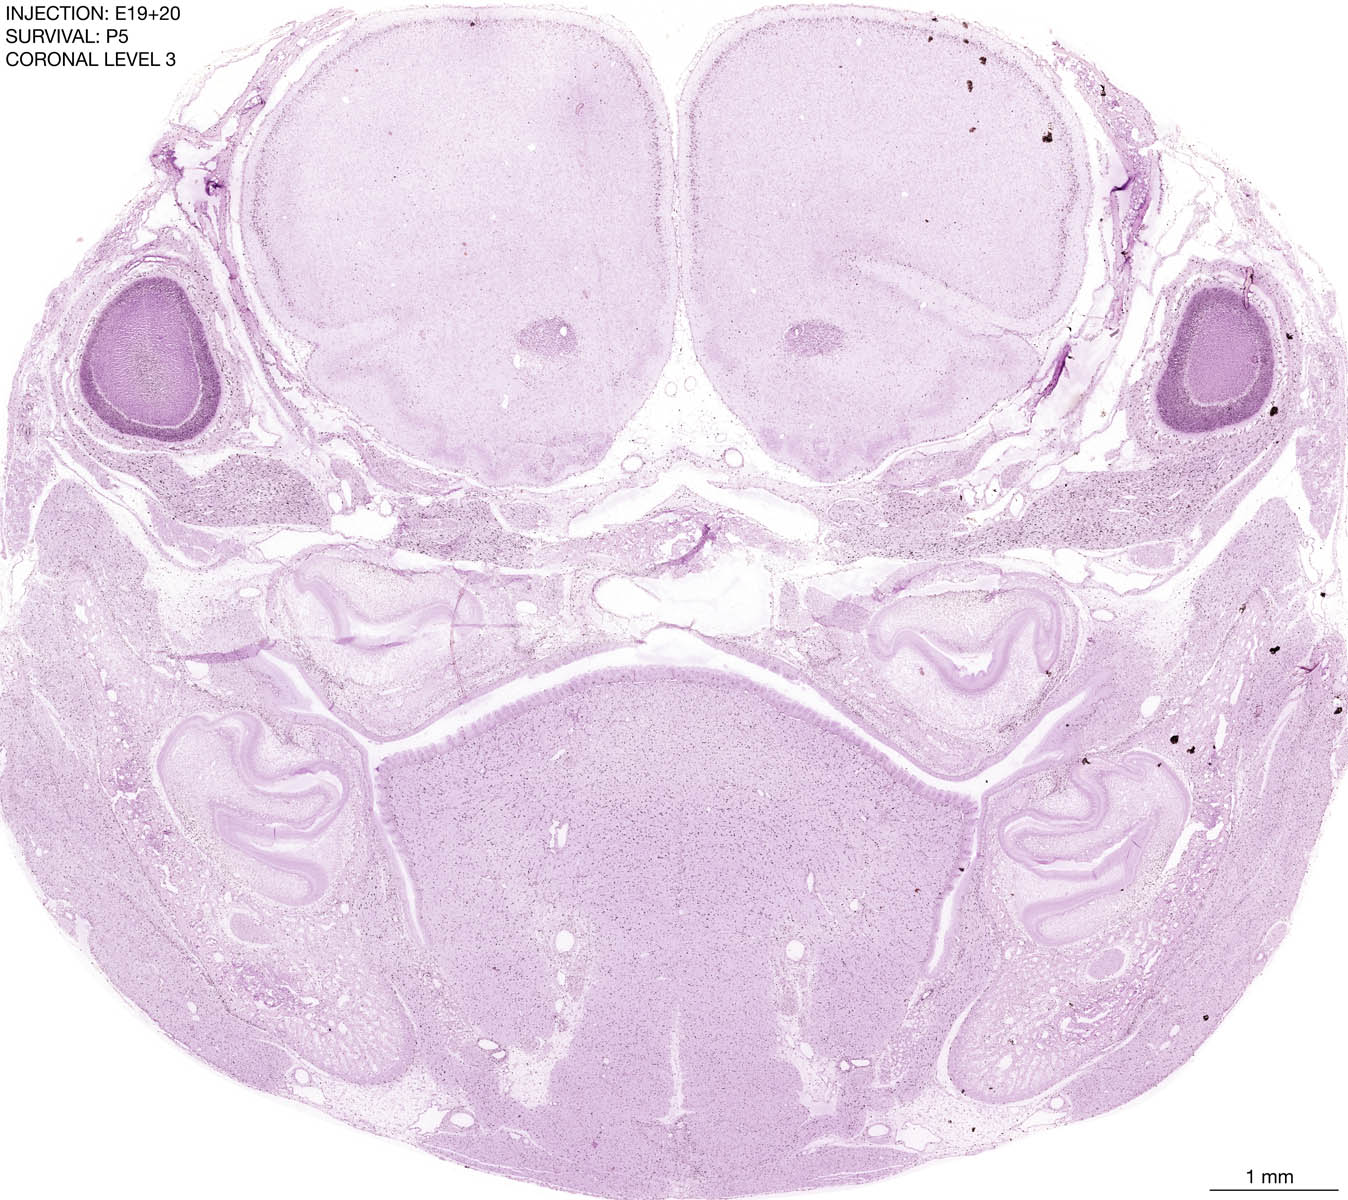

E19+20 P5 Survival The images below are from the brain of a rat that was exposed to tritiated thymidine on E19+20 and survived to P5. Download: Large | High Res Download: Large | High Res Download: Large | High Res Download: Large | High Res Download: Large | High Res Download: Large | High Res Download: Large | High Res Download: Large | High Res Download: Large | High Res Download: Large | High Res Download: Large | High Res Download: Large | High Res Download: Large | High Res Download: Large | High Res Download: Large | High Res Download: Large | High Res Download: Large | High Res Download: Large | High Res Download: Large | High Res Download: Large | High Res Download: Large | High Res Download: Large | High Res Download: Large | High Res Download: Large | High Res Download: Large | High Res Download: Large | High Res Download: Large | High Res Download: Large | High Res